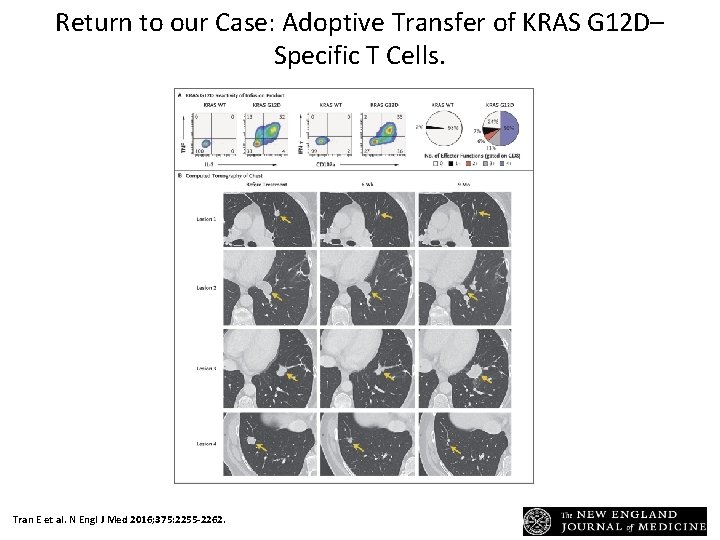

Return to our Case: Adoptive Transfer of KRAS G 12 D– Specific T Cells. Tran E et al. N Engl J Med 2016; 375: 2255 -2262.